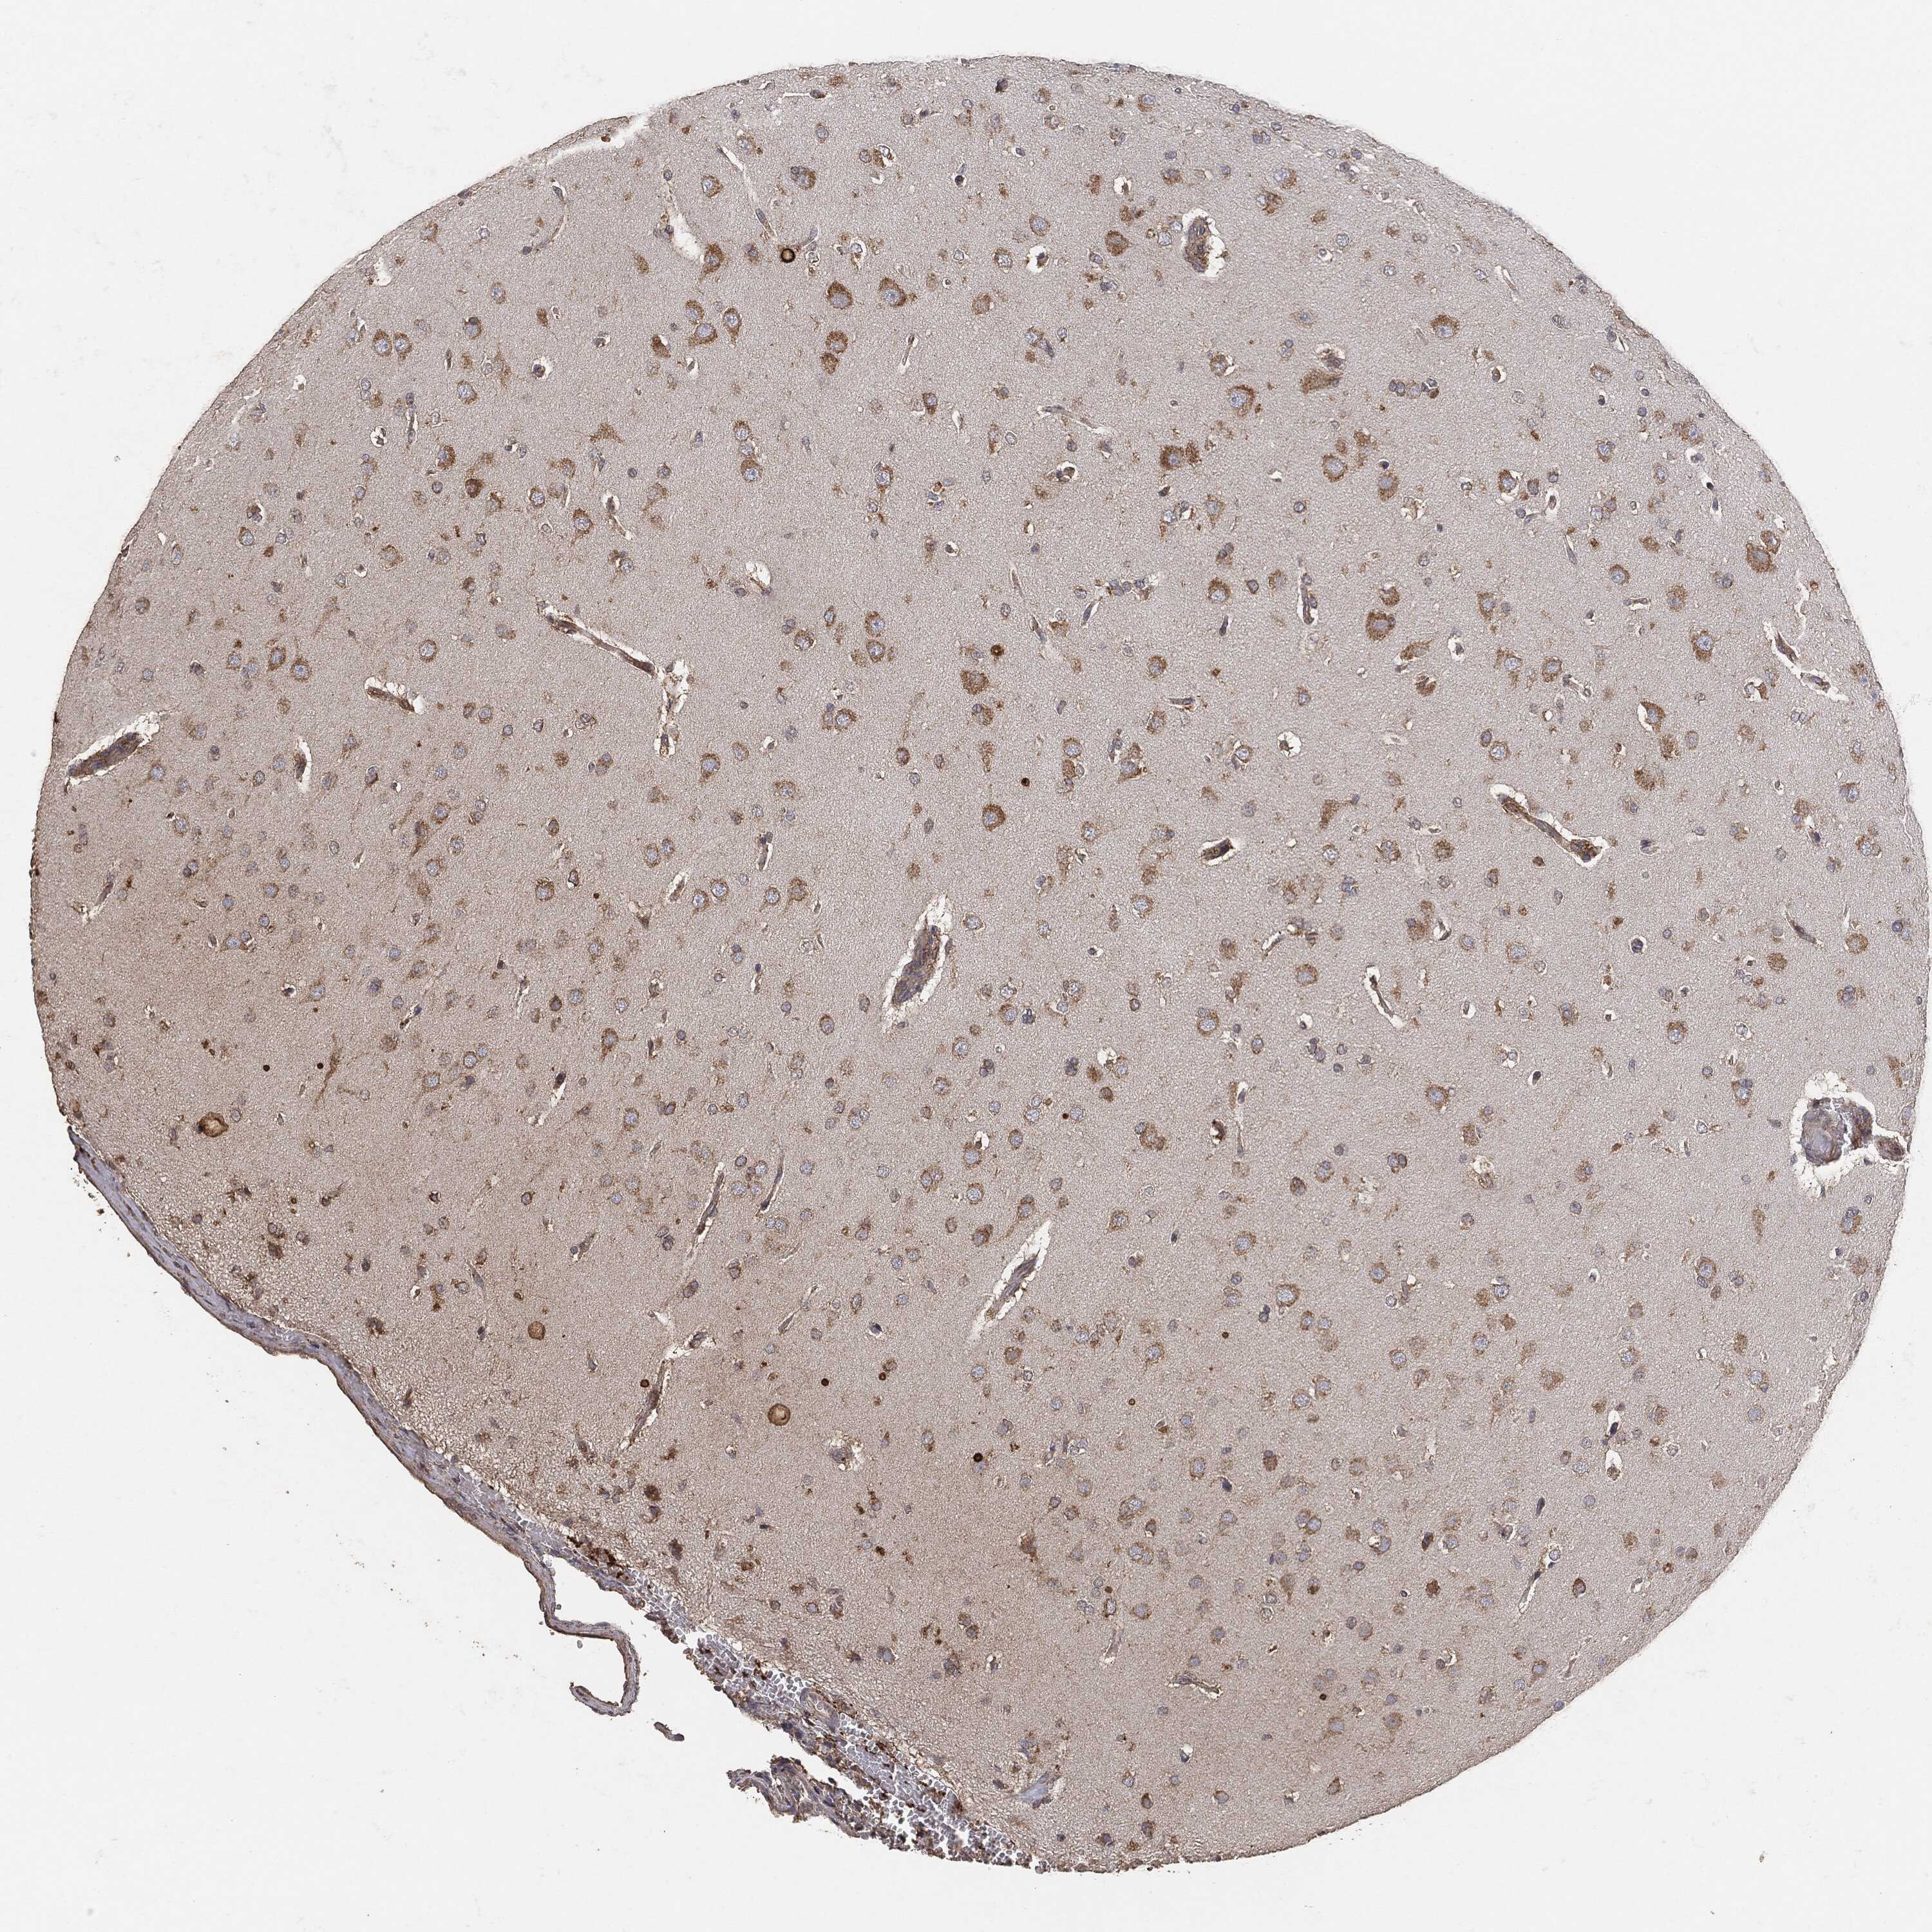

GLIOMA - Protein expressioni

A mouse-over function shows sample information and annotation data. Click on an image to view it in a full screen mode. Samples can be filtered based on level of antibody staining by selecting one or several of the following categories: high, medium, low and not detected. The assay and annotation is described here.

Note that samples used for immunohistochemistry by the Human Protein Atlas do not correspond to samples in the TCGA dataset.

Antibody stainingi

Antibody staining in the annotated cell types in the current human tissue is reported as not detected, low, medium, or high, based on conventional immunohistochemistry profiling in selected tissues. This score is based on the combination of the staining intensity and fraction of stained cells.

Each image is clickable and will lead to virtual microscopy that enables deeper exploration of all samples and also displays staining intensity scores, fraction scores and subcellular localization as well as patient and tissue information for each sample.

Glioma, malignant, High grade

Glioma, malignant, Low grade

Glioma, malignant, NOS